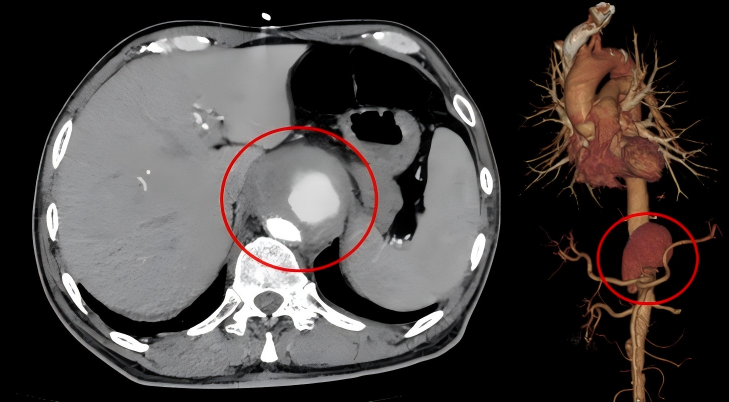

术前胸腹部CTA清晰显示,于先生的腹主动脉瘤体巨大,累及范围广泛,病变不仅侵蚀主动脉壁形成假性动脉瘤,还伴有多处夹层,更严重的是,病变直接侵犯了腹腔干动脉、肠系膜上动脉及双侧肾动脉等腹腔重要脏器供血的“生命之窗”,内脏器官血供受严重威胁。由于病变核心区域位于内脏动脉区,这一区域常规被视为腔内微创治疗的“禁区”,传统的腔内修复技术(TEVAR/EVAR)因无法兼顾重要分支血管的血流而难以实施。

术后即刻造影结果显示,巨大腹主动脉瘤体被完全隔绝,腹腔干、肠系膜上动脉、双侧肾动脉等所有重要内脏分支血管均血流通畅,支架定位精准。于先生术后恢复顺利,长期困扰的腹痛症状完全消失,且无并发症。令人欣喜的是,术后1个月的CTA随访复查显示,所有支架及分支血管均保持通畅,动脉瘤隔绝效果完美,无明显内漏。